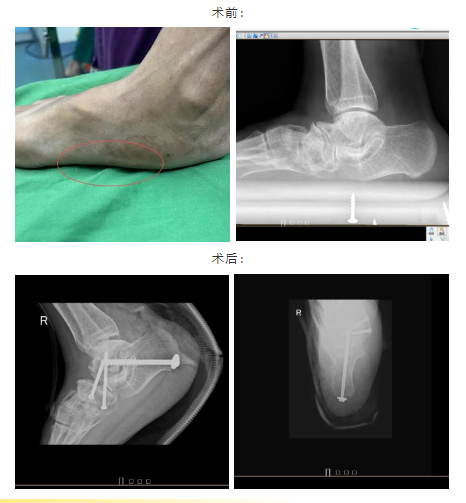

近日,茂名市人民医院骨科中心肖进教授团队成功施行了茂名首例成人扁平足矫正手术,解决了患者多年来行走疼痛,无法体育锻炼等问题,这也是茂名市人民医院在骨科领域的又一次新突破。

“您这种情况的话,保守治疗已经无法从根本上解决问题,也没办法解决扁平足导致的疼痛,建议您进行手术治疗。这种手术可以矫正您的扁平足畸形,并且明显改善疼痛症状,以后可以无痛行走,效果很不错的。”肖进主任在认真检查患者陈先生的身体情况并评估病情后,提出了进行手术矫形的诊疗建议。经患者及家属同意后,由肖进主任主刀为患者实施了扁平足矫形手术,用时仅大约一小时,手术过程顺利,陈先生的扁平足畸形得到纠正并顺利出院。后续经过门诊复诊指导进行功能锻炼后,陈先生目前术后恢复良好,足部疼痛症状已消失。

“与儿童扁平足矫正方法不同,成人扁平足的矫正会更复杂困难,技术要求更高。”肖进主任说道,“成年人的扁平足有的是先天的,也有的是后天的。对于后天性平足(医学上称为“成人获得性平足症”),根据病理改变的不同,可以分为4期,每个阶段治疗原则不尽相同。有的可以保守治疗,有的需要手术。不同情况下手术方式的选择也不同。比如此次的病友陈先生因为患病时间长,就诊时为僵硬性平足,已经出现足部关节退变,所以选择了足部三关节融合术这种手术方式。”